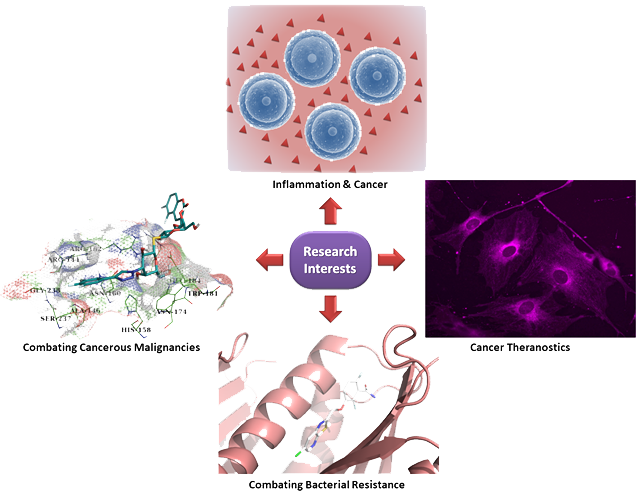

Cancer as a condition refers in abnormal and uncontrolled cell growth across any organ or tissue of the body, remaining still unaddressed until today with treatment issues like general toxicity, side effects, relapse and emerging drug resistance. Appearance and progression of the disease are based on complex and multifactorial etiologies. Among the most important proteins recognized and implicated in numerous cancer hallmarks & inflammatory processes are Galectins. This family of proteins showcases cancer specific functions and their abundant expression in such malignant conditions makes them appealing targets for inhibition or modulation giving space for the development of novel cancer treatments.

The existing coherence among cancer and inflammation has been really old and dates back to the late 19th century, where scientists hypothesized that cancer appears where the immunoresponse cells are invading existing inflamed sites. Until today the mechanism is not clearly known but they share common pathways like proliferation, migration, angiogenesis and cell survival. Although inflammation possess a normal immunoresponse to endogenous or exogenous stimuli, chronic inflammation is associated with elevated risk for several diseases occurrence. Moreover, cancer cells show high plasticity in contrast to cancer-associated inflammatory cells that are genetically stable and strategically this could be exploited to circumvent emerging drug resistant cancers.

The emerging field of ‘Cancer Theranostics’, arises as a cutting-edge approach offering a valuable combination of cancer diagnosis and therapy, aiming to provide early diagnosis, more accurate molecular imaging and precise treatment options. The necessity for accurate diagnosis and treatment at the right time, could be served as a promising and successful modality to alleviate the development and progress of cancer, in a way to improve the survival rate and subsequently the quality of patients lives. Until today, numerous Theranostic probes have been developed and already established as tools for cancer precision and personalized medicine. Therefore, the need for further development of innovative theranostic ‘smart’ probes still remains an urgent topic.

The emergence of resistant pathogens to antibacterial drugs is becoming one of the most serious threats of the future global health. This became even more apparent the past two years of the pandemic with the witnessed wave of increasing pressure to national health systems. Hence, rising resistance of pathogens to currently available therapies exhibits a consecutive decline of successful infection treatments. The research interest on identifying novel bacterial targets in order to combat resistant strains is continuous and several promising targets have been identified so far. Amongst them are factors directly implicated in bacterial cell divisions that show great interest, given the fact they are highly conserved and posses potent antibacterial activity over drug resistant pathogens.